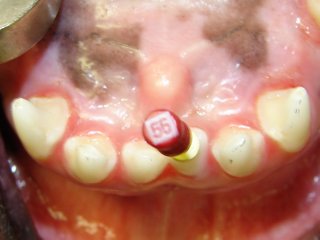

A fractured upper incisor’s pulp chamber and root canal are being cleaned with an endodontic file.